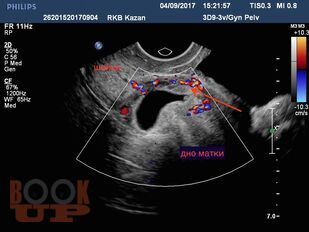

В методических рекомендациях приведен сравнительный анализ существующих методов лечения беременности в рубце на матке после кесарева сечения в нижнем сегменте. Подробно изложен собственный запатентованный протокол лечения рубцовой беременности в зависимости от данных ультразвукового исследования в совокупности с уровнем ХГЧ в сыворотке крови беременной, разработанный авторами. Данный протокол позволяет на основании полученных диагностических данных выбрать оптимальный метод органосохраняющего лечения, определить методы последующего контроля состояния пациента.